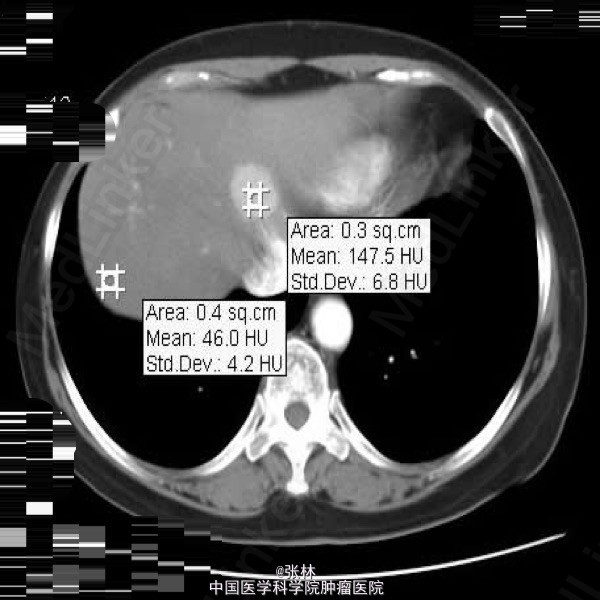

【影像表现】:肝脏形态正常,边缘光整,于肝S4段可见3×2.5cm大小稍高密度,边界清,增强扫描均匀强化,门脉期及延时扫描持续呈稍高密度;肝右叶可见密度降低。余胆、脾、胰、双肾未见异常;腹膜后未见肿大淋巴结。

【影像诊断】:肝S4段不典型血管瘤【诊断要点】:增强扫描均匀强化,门脉期及延时扫描持续呈稍高密度。